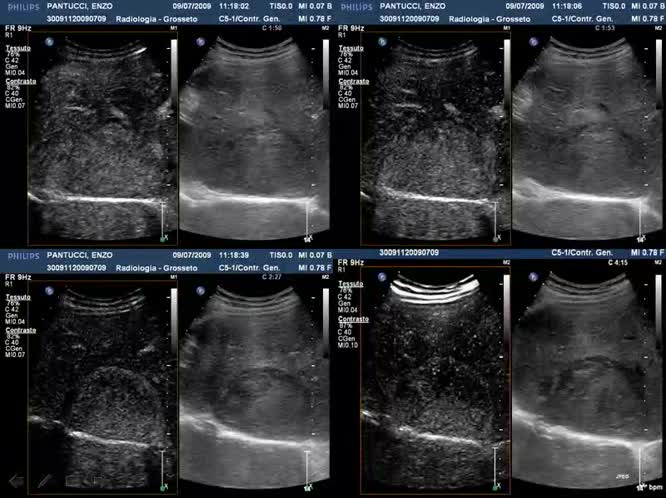

02 - Epatocarcinoma Imaging diagnostico

Congresso

: Approccio Integrato all'Epatocarcinoma

Autori

: MC. della Pina |

Data

: 06 febbraio, 2010 |

Lingua

: ITA |